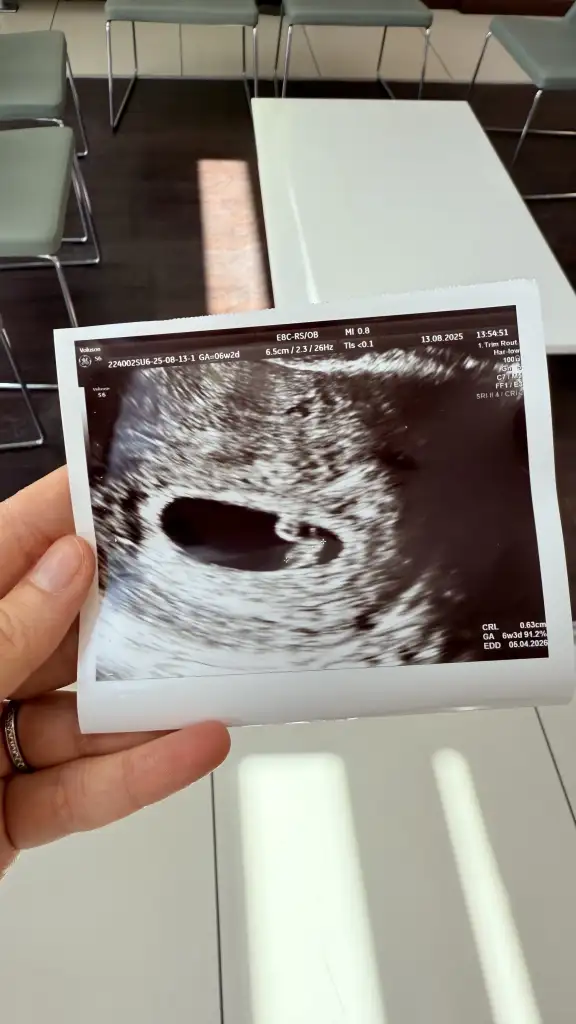

Merhaba saglikla kucaginiza alingünaydınn, bugün keseyi gördük çok şükür. karından baktı sadece. haftaya cuma kalp atışı için gidicez inşallah

Oy maşallahkızlarrr bugün kalp atışını duydukçok yüksek sesle duyamadık ama daha küçük olduğu için normal dedi doktor. Son adete göre 6+2 ama gelişimi 2 gün önden gidiyor dedi hayırlısı bakalım

dün gittim keseyi gördük, haftaya cuma kalp atışı için çağırdı. siz?Sat tarihlerimiz aynı hiç gittiniz mi doktora?

Ben de pazartesi gittim kese için 5+6 dedi ama yolk sac vs görünmedi haftaya çağırdı beni dedün gittim keseyi gördük, haftaya cuma kalp atışı için çağırdı. siz?

bende de yolk sac görmedi, kese 6.8mm gördü. 5haftaya uygun dedi. haftaya hangi gün gideceksiniz :) ay çok heyecenlı yaBen de pazartesi gittim kese için 5+6 dedi ama yolk sac vs görünmedi haftaya çağırdı beni desizde kese boyutu kac cikti?